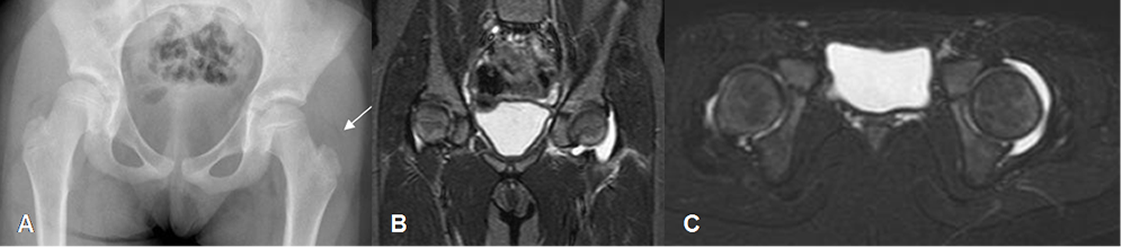

Con la radiografía se puede encontrar derrame articular, por el desplazamiento de los cojinetes grasos, en la fase inicial. Luego hay disminución del espacio, por destrucción del cartílago articular. Finalmente aparece erosión y destrucción del hueso subcondral. (2). (Fig 142 A y B).

La ecografía juega un papel importante para detectar el derrame articular y dirigir la punción, que permite confirmar el diagnóstico. (2). (Fig 142 C).

Fig 142 A. Artritis infecciosa.

A: Rx AP. Desplazamiento lateral del cojinete graso glúteo, que hace sospechar derrame articular.

B: RM coronal y C: RM axial en STIR. Se confirma el derrame articular, por artritis infecciosa.